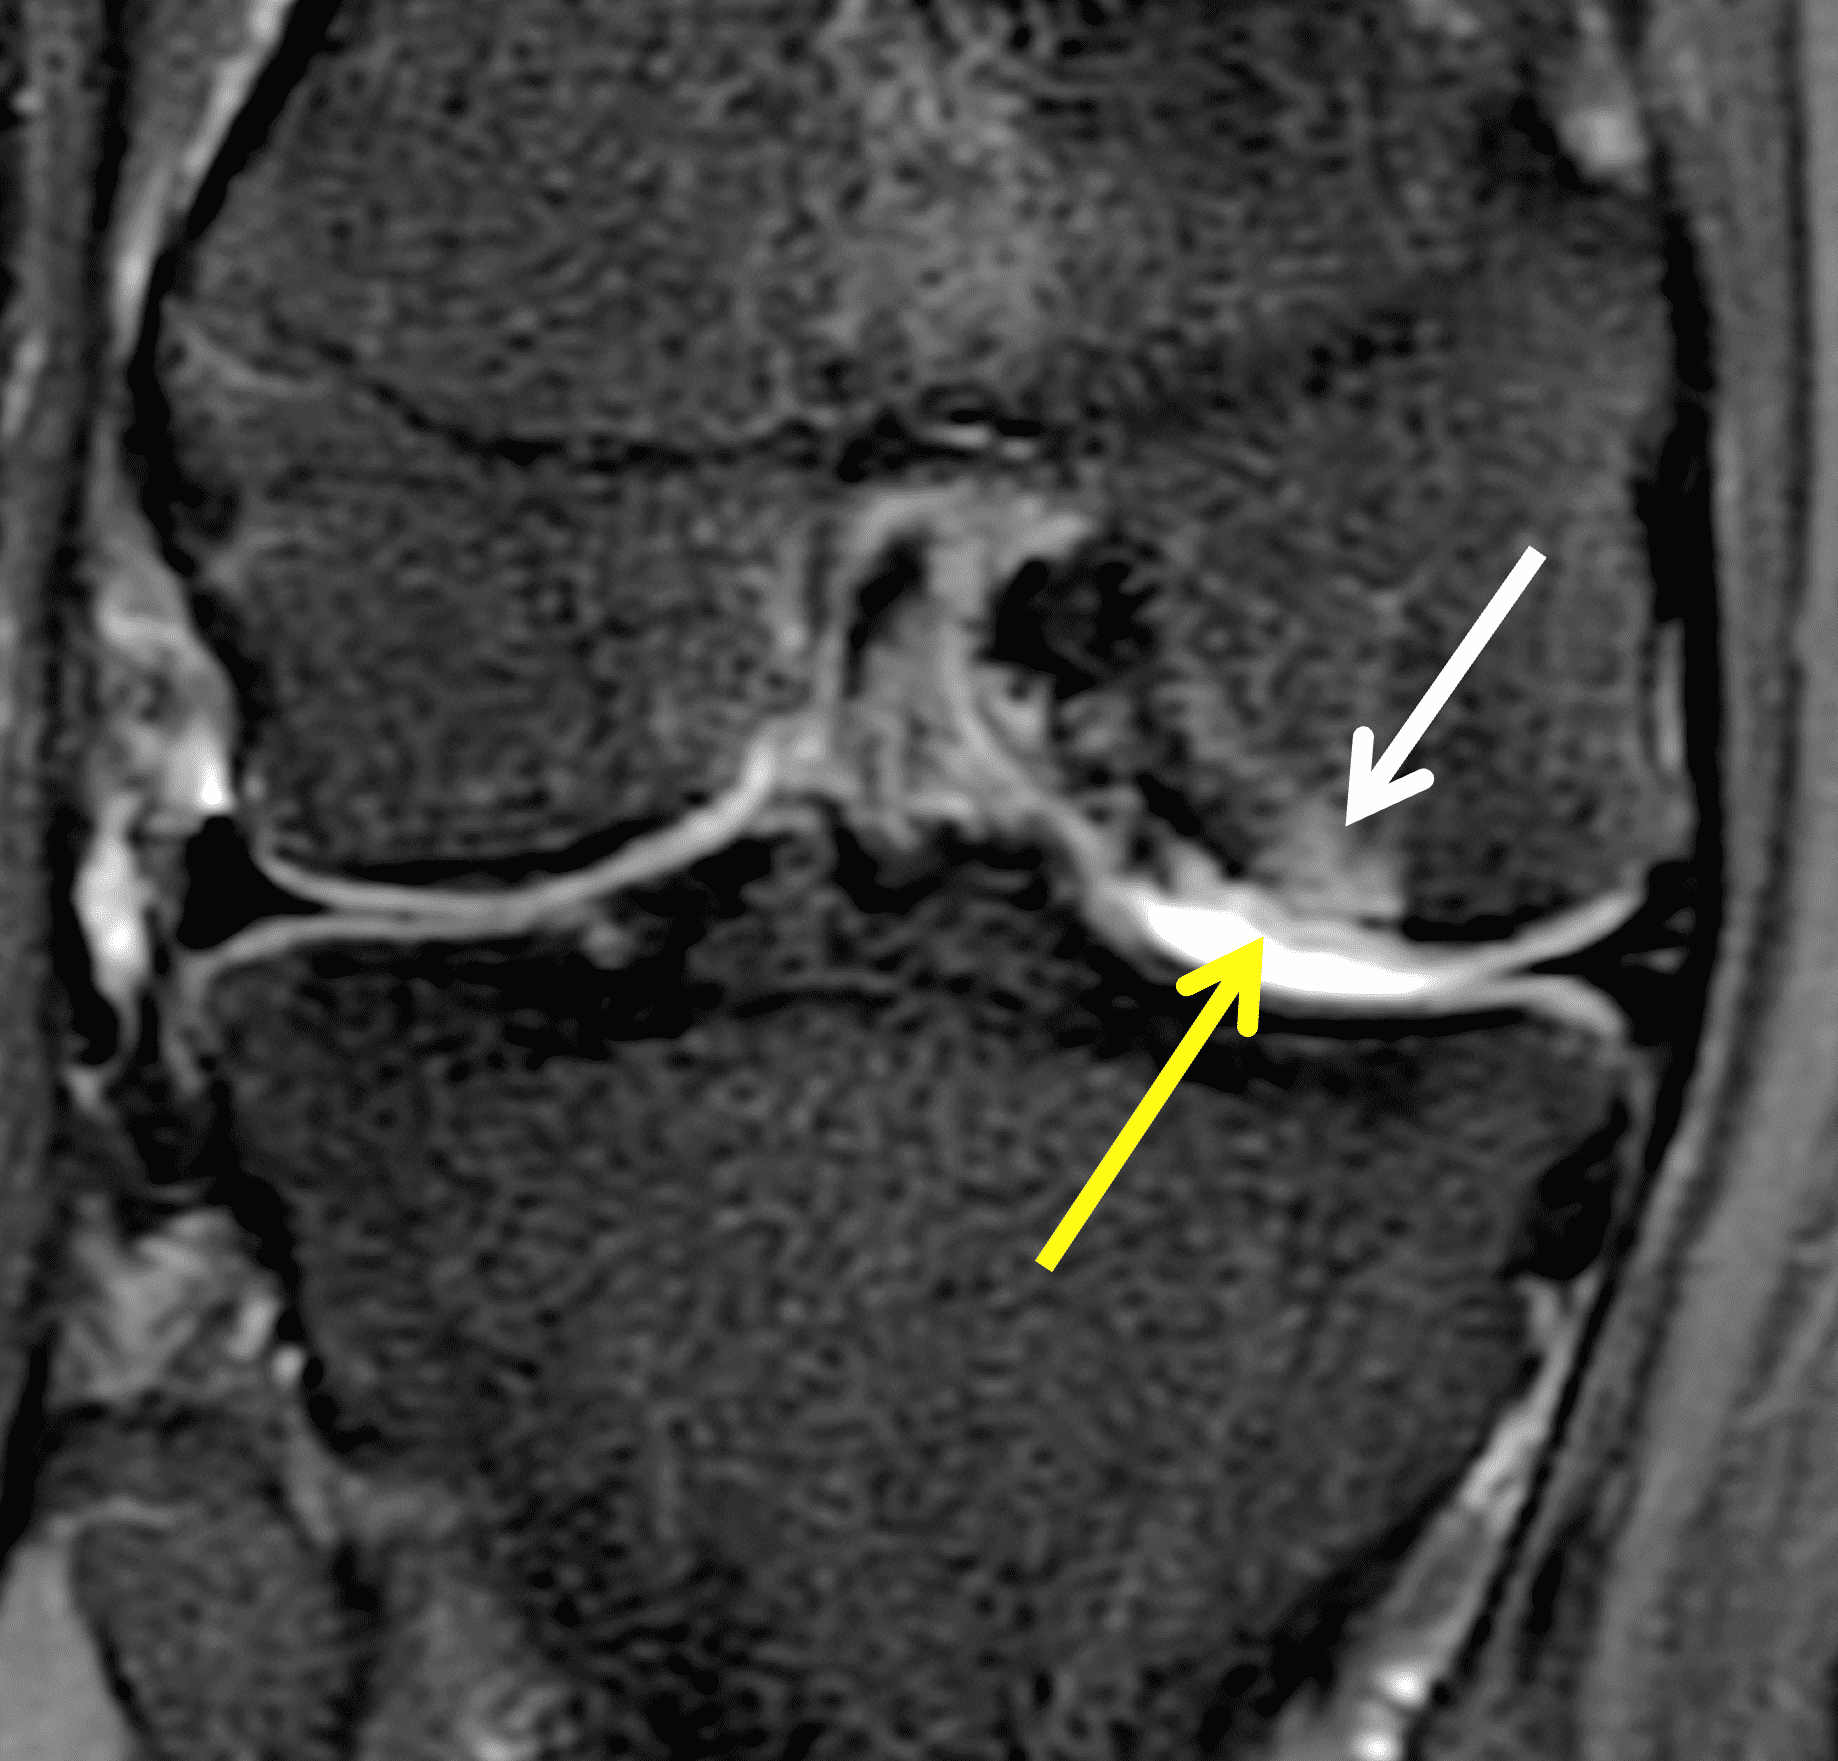

A 32-year-old man suffered a traumatic chondral injury to the medial femoral condyle that was treated with an osteochondral allograft 20 months previously. Representative images from a current knee MRI include (1A) coronal fat-suppressed fluid-sensitive and sagittal (1B) T1-weighted, (1C) proton density-weighted, and (1D) T2-weighted sequences. Are the post-operative MRI findings normal and expected, or abnormal and pathologic? Based on these images, would you characterize the procedure as a success or failure?

Figure 2: (2A) On the coronal image, the margins of the osteochondral graft are faintly visible (arrowheads). Both the graft and underlying bone show mild marrow edema, an expected finding. (2B) The T1-weighted image shows continuity of the marrow in the graft (asterisks) with the underlying bone, indicating osseous integration. A bioabsorbable pin (arrow) used for graft fixation is partly visible. (2C) The proton density-weighted image shows a low signal intensity seam (black arrow) between the native cartilage and transplant, as well as a defect in the subchondral bone plate of the graft (red arrow) where the pin was drilled, both normal findings. (2D) The T2-weighted image shows a smooth, congruent articular surface (arrows), restoring the normal anatomy, and a tiny subchondral cyst. No findings are present to suggest graft failure. The patient’s current symptoms were attributed to pathology elsewhere in the joint (not shown).

Successful osteochondral allograft procedure.

The postoperative imaging appearance of osteochondral allografts is similar to autografts (Figure 2).33 The subchondral bone plate of the donor and recipient sites do not have to match, but the articular surface should be congruent. Grafts that fail to incorporate by one year have a poor prognosis. Persistent marrow edema (beyond 12 months), a thick graft interface containing cysts or fluid, and subsidence of the graft are associated with poor osseous healing and worse outcomes. Extensive host marrow edema and severe synovitis may be a clue to immunologic rejection of the graft (Figure 18).21, 34